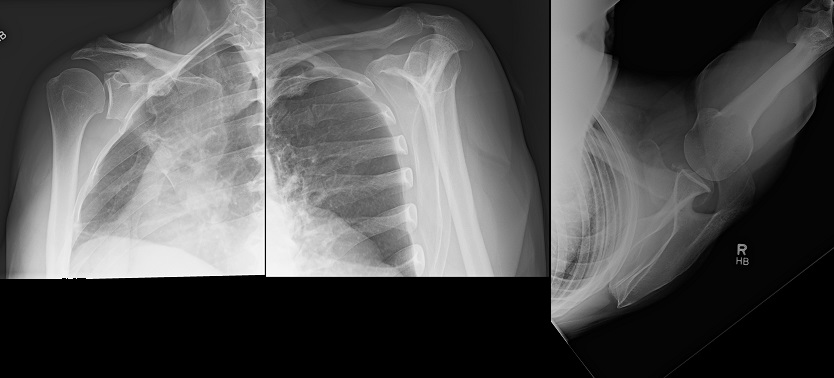

An 80 year old female presents to your office with a left ring finger deformity after a fall one week ago. She initially went to urgent care and xrays were unremarkable for a fracture (Figures 1 and 2). A photo of her left ring finger is shown in figure 3. On physical exam the left ring finger is in hyperextension at the PIP joint and flexion at the DIP joint. She able to flex her PIP joint with full motion. What is the best treatment option?